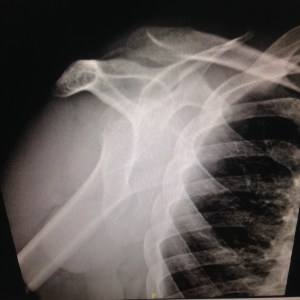

However, this Ramadan is slightly different for us, a challenging one in fact. On the 3rd day of Ramadan CheeseBoy slipped and fell, and had his shoulder dislocated. The emergency doctors at the hospital had to put CheeseBoy to sleep in order to fix his shoulder. Poor him.

The X-Ray before the fixing (Seriously peeps I am certainly clueless looking at this)